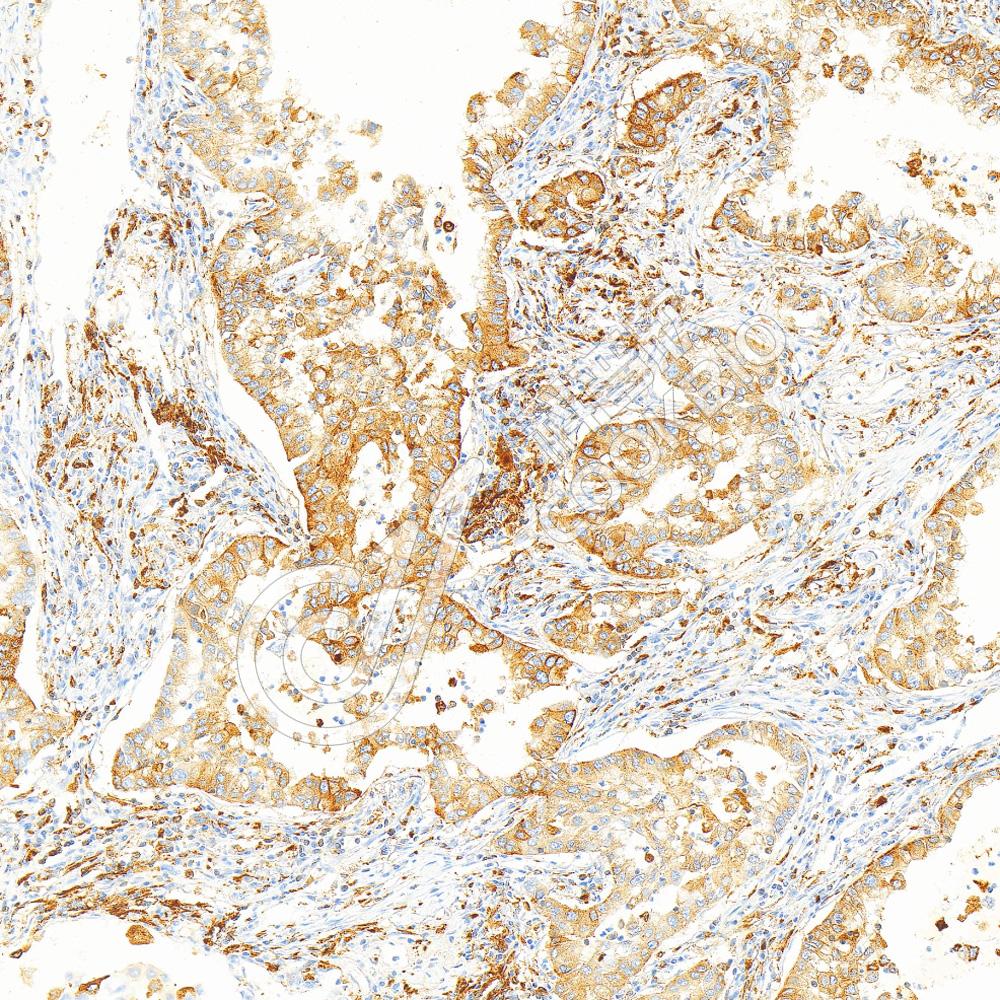

IHC检测MHC Class II蛋白(货号 K5450279).

样品: 人食管癌, 4%多聚甲醛 (货号KSG1101) 固定12-24小时.

抗原修复: Tris-EDTA抗原修复液(pH 9.0) (KSG1203), 100℃, 25分钟.

—抗: 1: 1000稀释, 4℃ 孵育过夜.

二抗: S-vision免疫组化多聚二抗(山羊抗兔),即用型 (货号KB3906), 室温孵育20分钟.

样品: 人肺癌, 4%多聚甲醛 (货号KSG1101) 固定12-24小时.